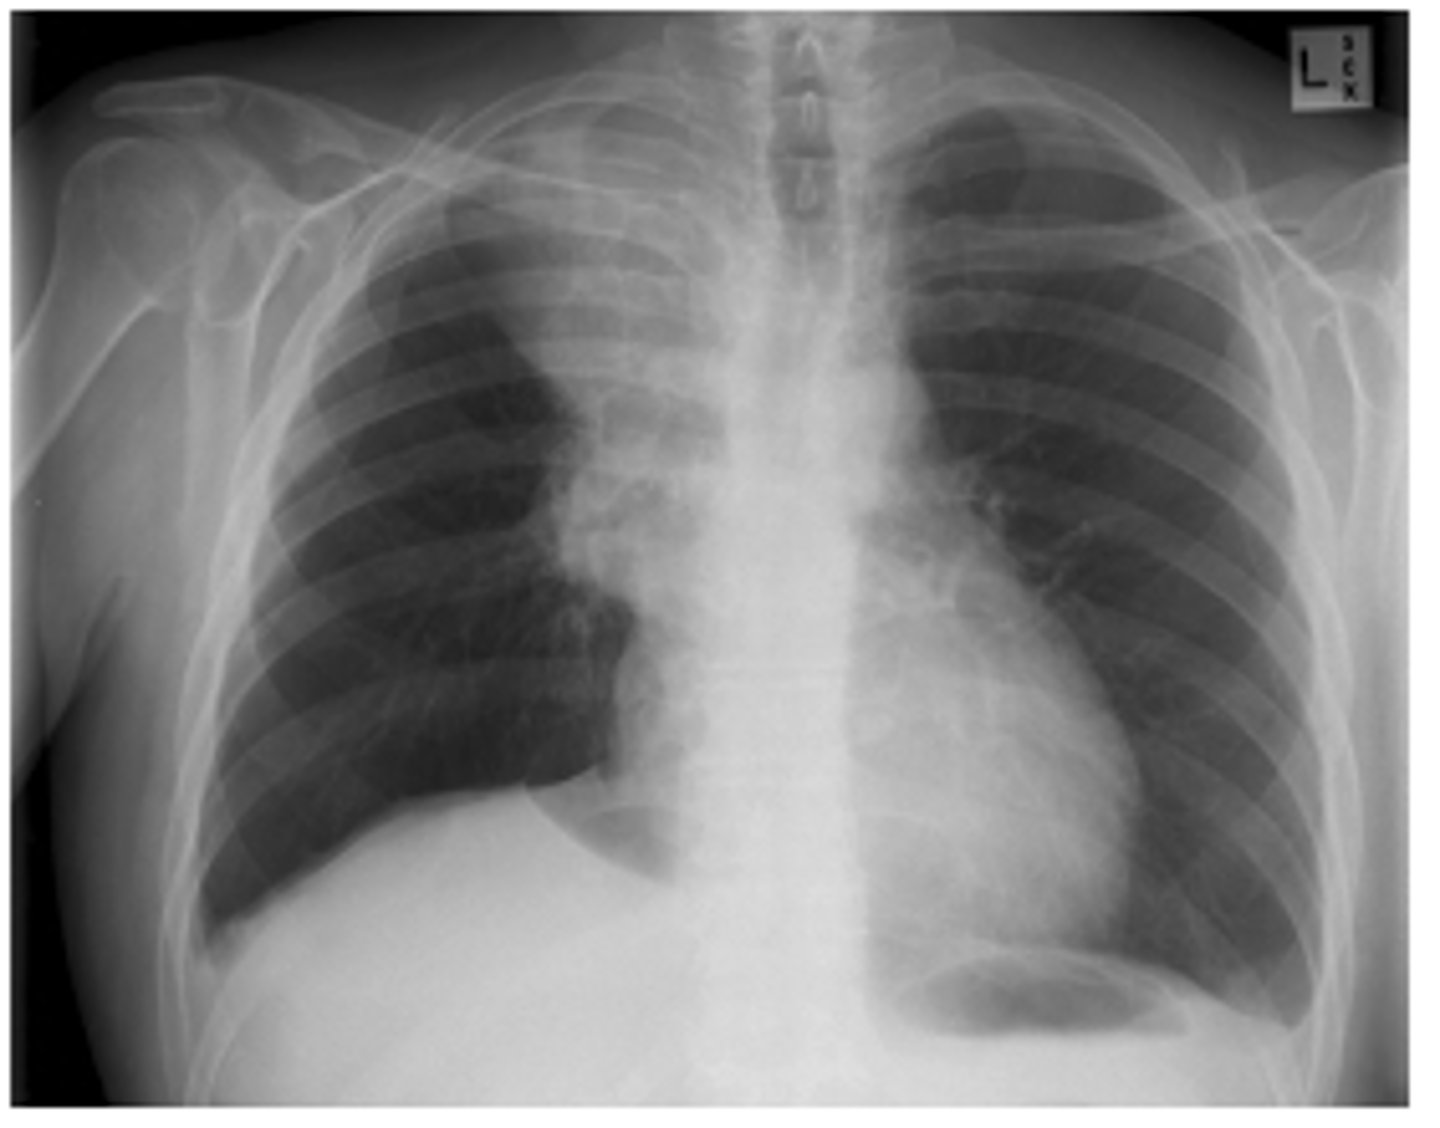

What is the silhouette sign? What does it help determine?

oHelps determine the location of an abnormality in comparison to normal anatomy.

oLoss of a normal border and contour occurs if there is an abnormality contiguous with that structure (next to)

EX: if the R cardiac border is obscured, then the infiltrate must be in the medial segment of the R middle lobe.

(pic also has spine sign)

<p>oHelps determine the location of an abnormality in comparison to normal anatomy.</p><p>oLoss of a normal border and contour occurs if there is an abnormality contiguous with that structure (next to)</p><p>EX: if the R cardiac border is obscured, then the infiltrate must be in the medial segment of the R middle lobe.</p><p>(pic also has spine sign)</p>

ID sign on back and finding

RML pneumonia obscuring the cardiac border but not the R hemidiaphragm. Note the triangular density on the lateral view.

<p>RML pneumonia obscuring the cardiac border but not the R hemidiaphragm. Note the triangular density on the lateral view.</p>